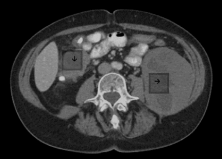

Figure 2. Transverse view of left retroperitoneal and paraduodenal mass

Horizontal arrow pointing to the left retroperitoneal mass extending from below the inferior pole of the left kidney into the pelvis. Vertical arrow pointing to the mass involving the second portion of the duodenum extending to the hepatic flexure.